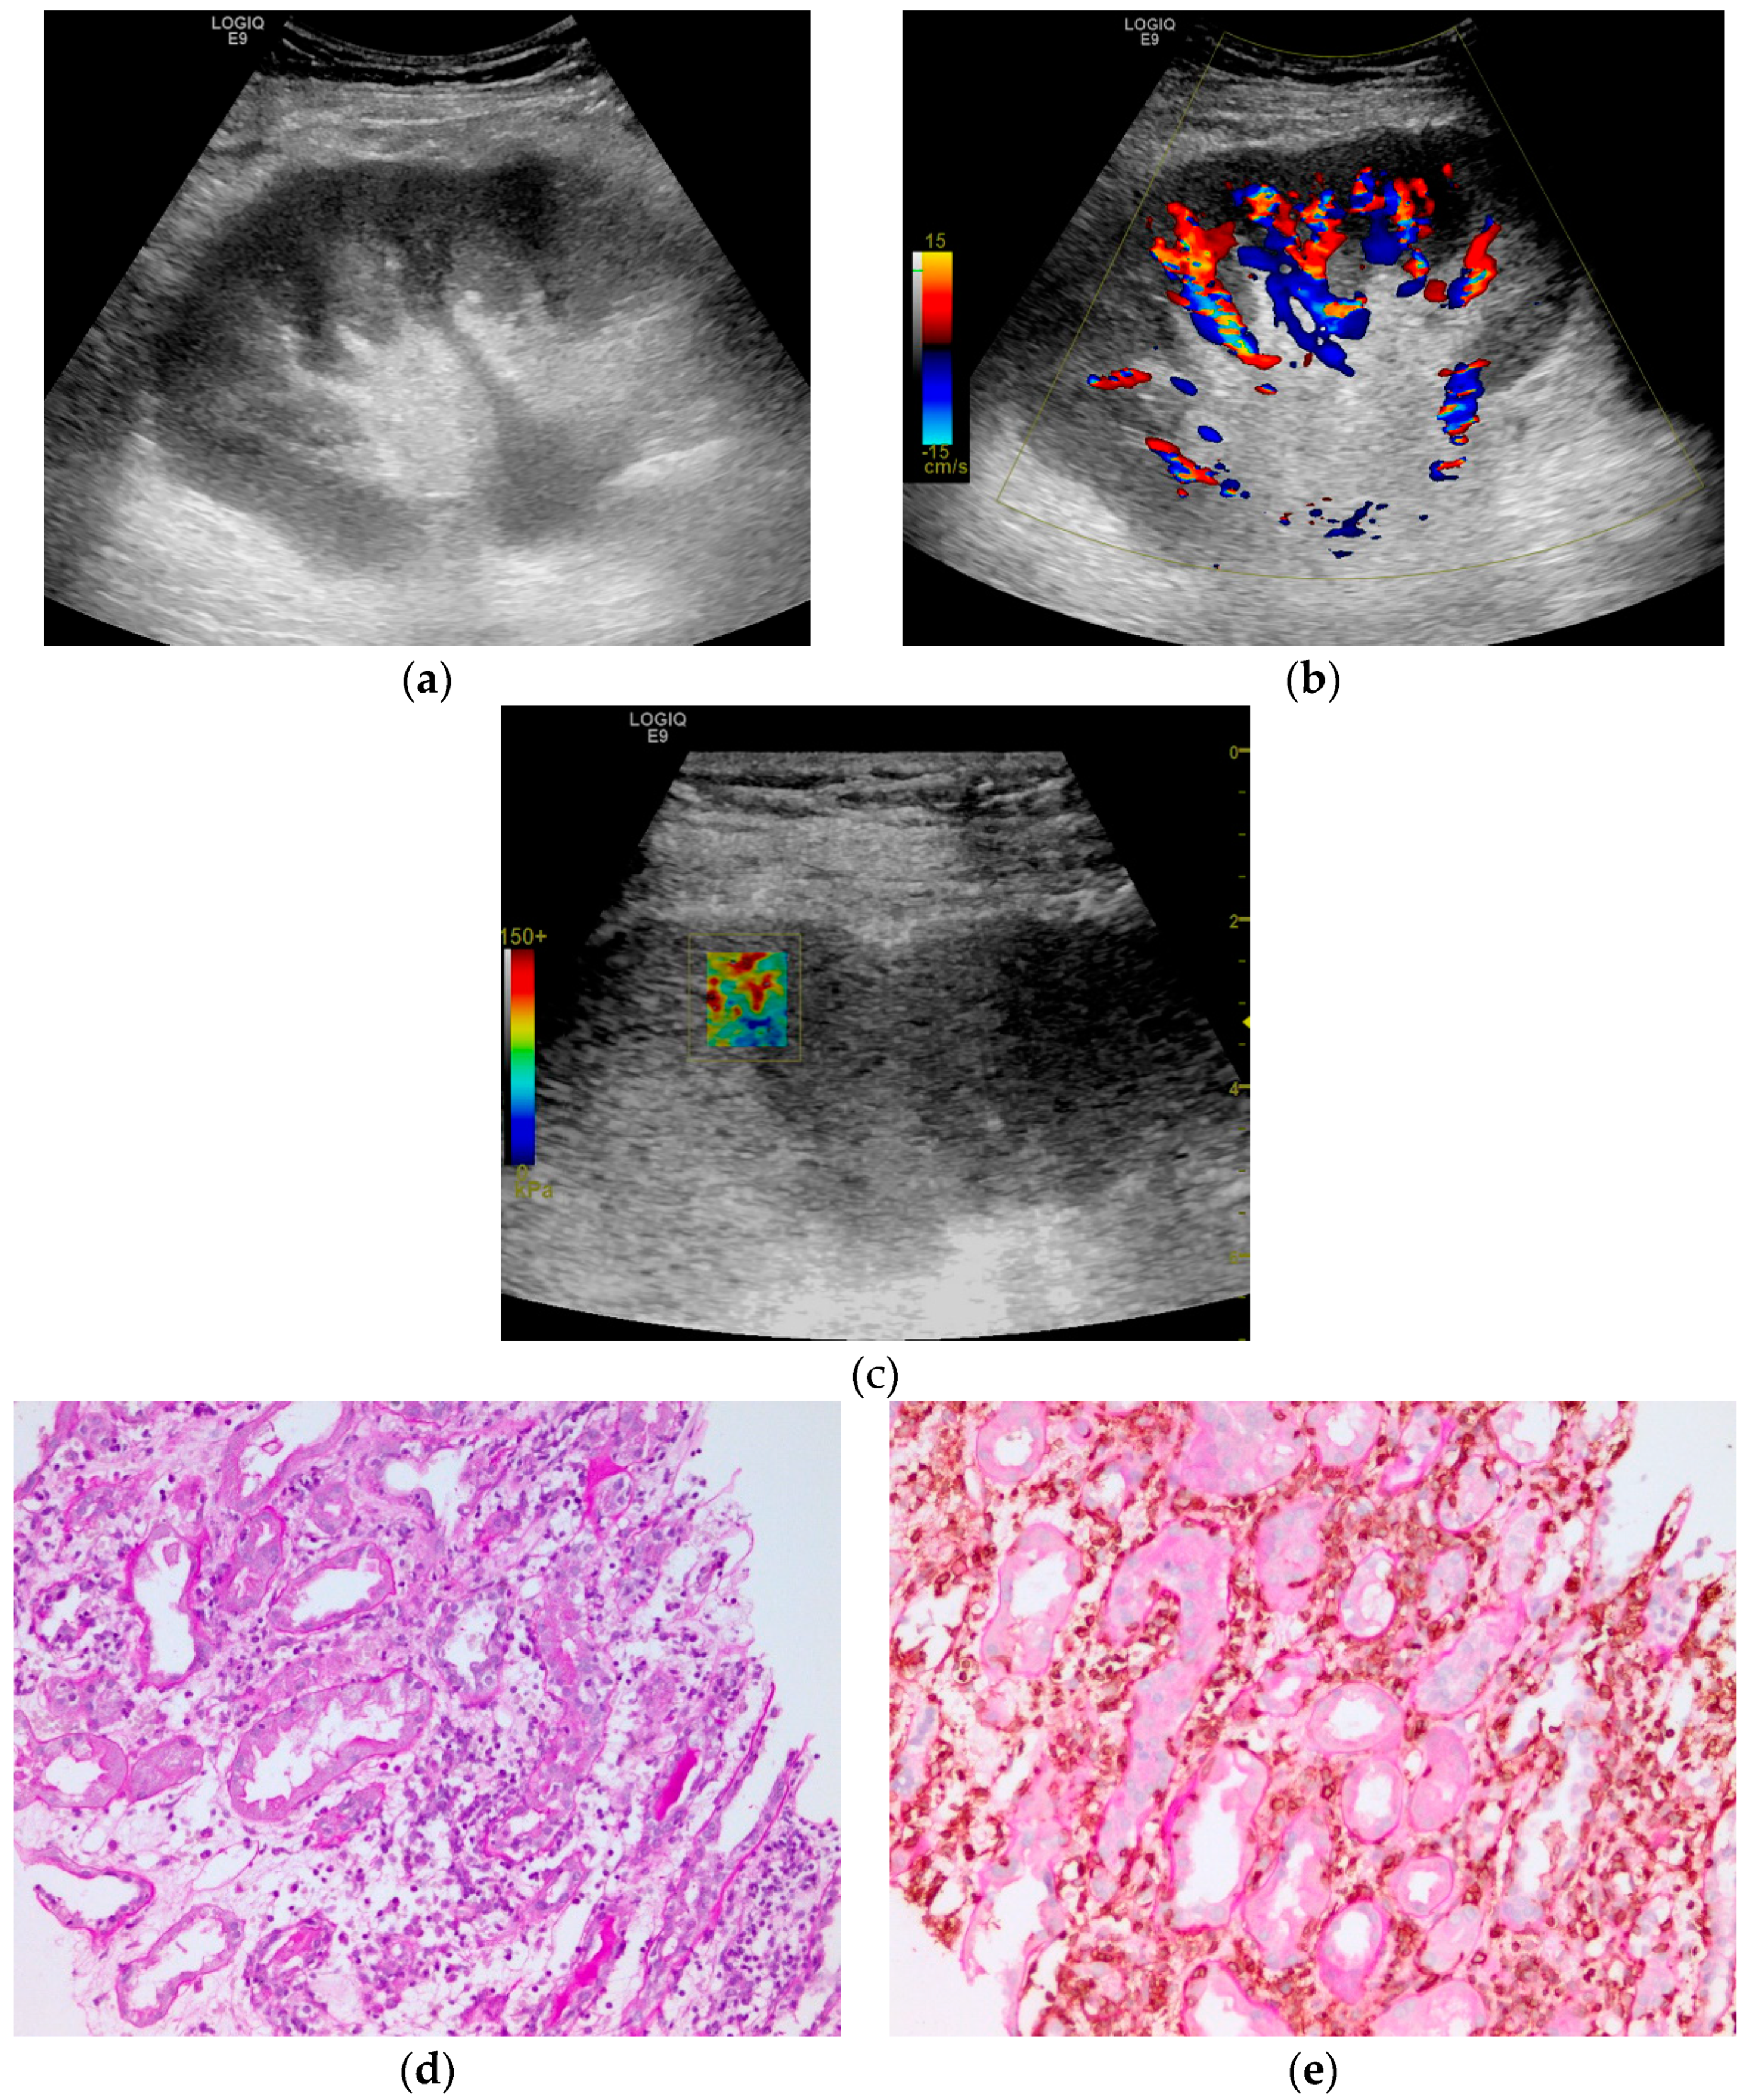

2.3. Grey Scale and Doppler Examination

2.4. Shear Wave Elastography Examination